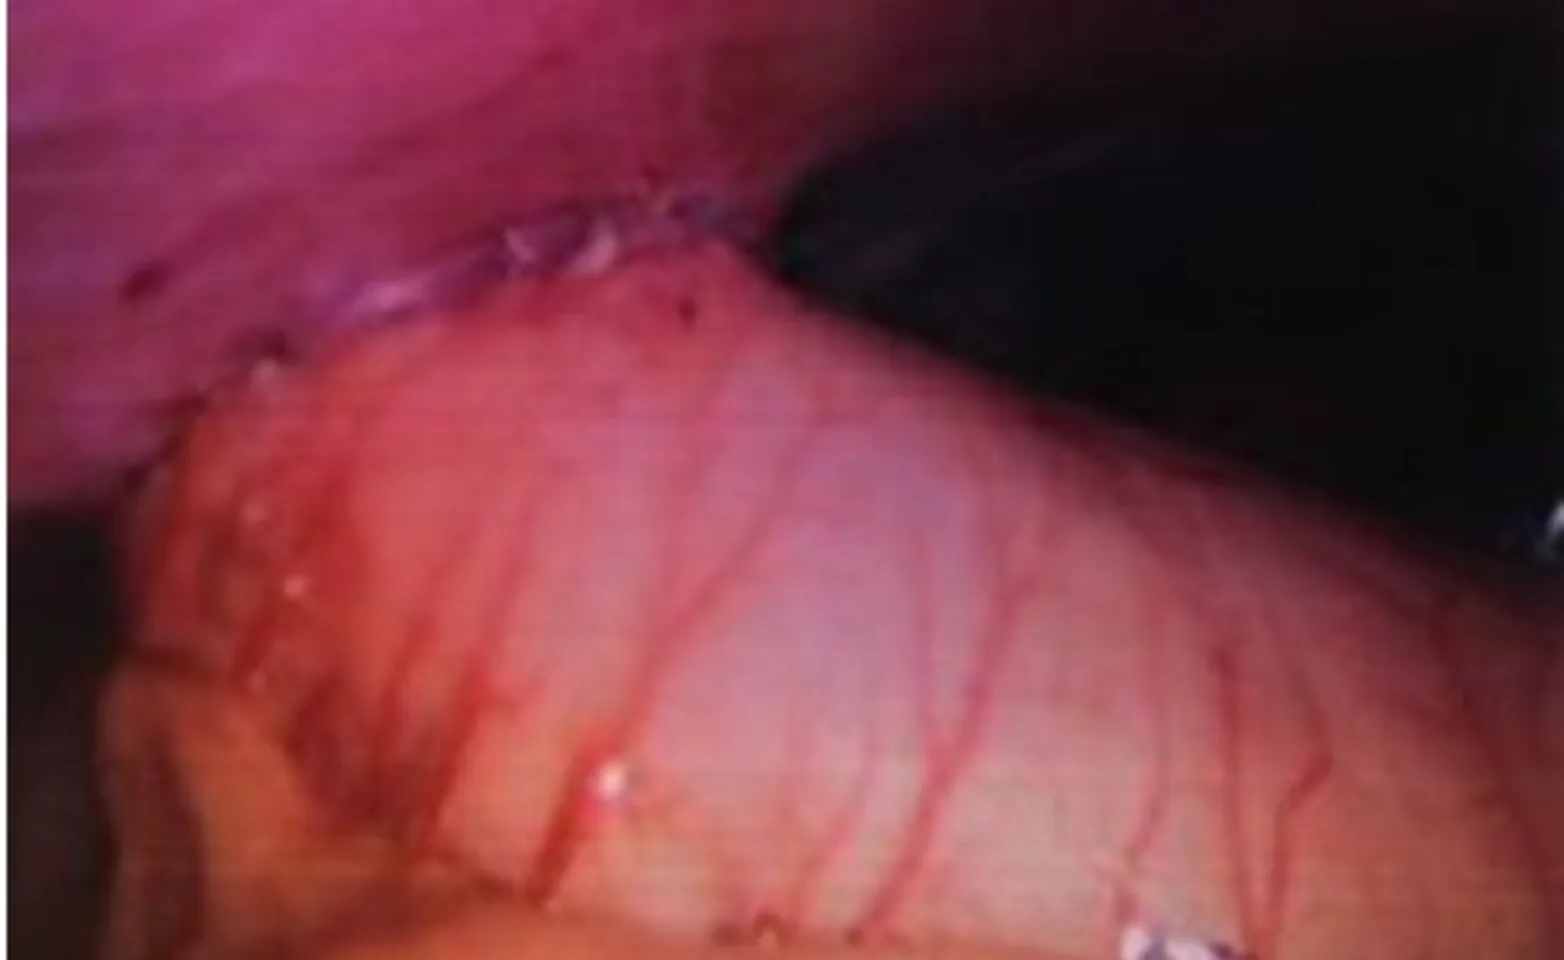

The use of laparoscopy to assist in gastropexy has become more popular in recent years because the surgery is less invasive. A rigid laparoscope is utilized to visualize and grasp the stomach, which is exteriorized through a small incision in the body wall. An incisional gastropexy is performed as described above through the small incision on the outside of the body. The gastropexy site is then visualized abdominally with the scope. (Figures 1-6 below)

Figure 3. The completed gastropexy, as seen by the laparoscope.